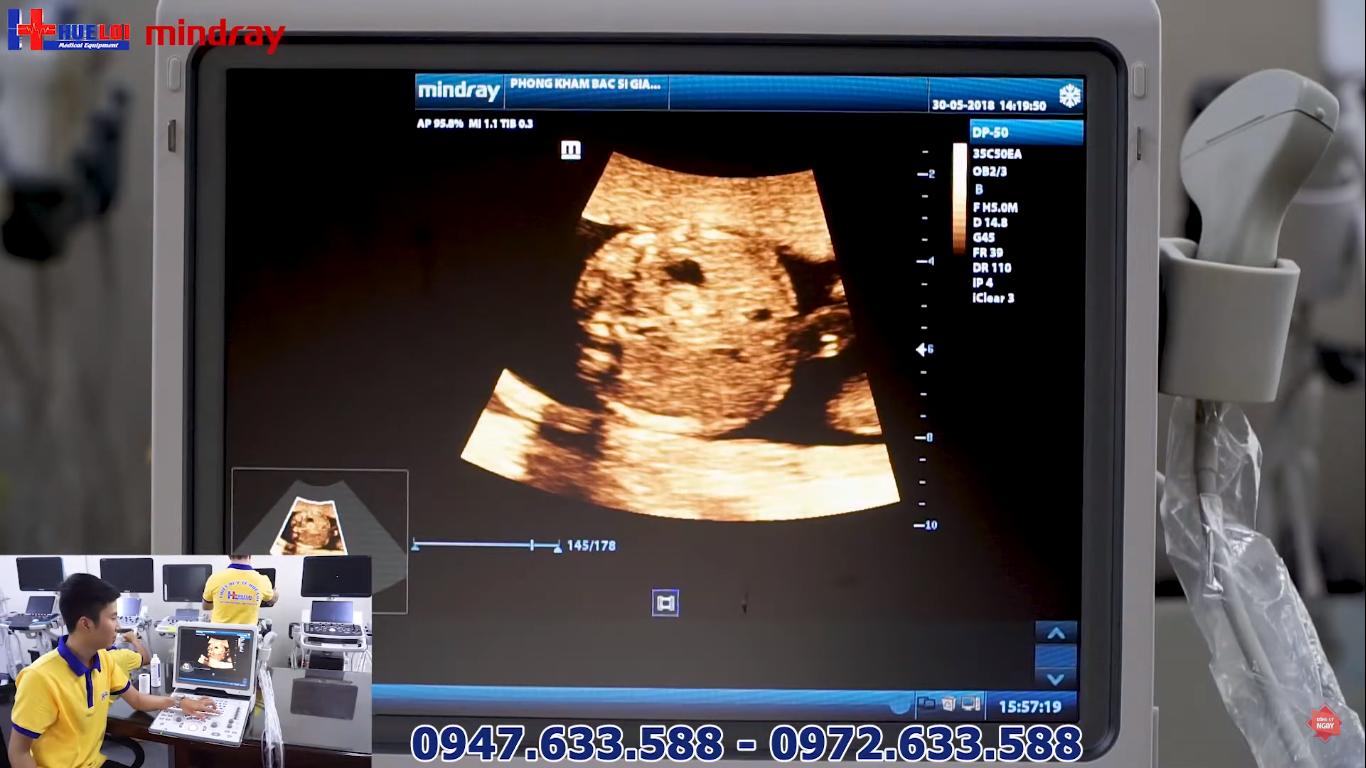

Chất lượng hình ảnh của Mindray DP 50:

2D ổ bụng - Đầu dò Convex